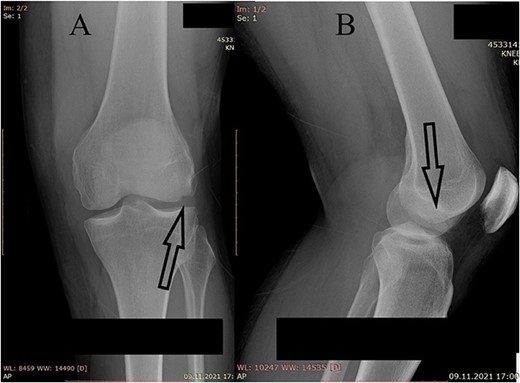

A plain X-ray of the left knee revealed a single defect of the lateral femoral condyle in the anteroposterior (AP) view. The lateral view showed a free bone fragment with a defect (Fig. 1A and B). Additional diagnostic imaging was performed. A computerized tomography (CT) scan revealed multifragmentary (three fragments) fracture of the lateral femoral condyle accompanied by a fracture of the left patella (Fig. 2). The fracture was classified as 33B3.2 according to the Association for Osteosynthesis–Orthopaedic Trauma Association (AO/OTA), Type II C (according to Letenneur) [2]. It was decided that single-approach surgery (posterior or anterior) would be insufficient for acceptable anatomic reduction and proper fixation of all the fragments because of the fracture complexity. The preoperative plan consisted of a posterior-first approach (extended posterior approach to the proximal tibia) for fixation of the largest (posterior) fragment (Fig. 3) followed by an arthroscopic anterior approach (for anterior fragment fixation). The predetermined time interval between the two procedures was to allow the healing of the joint capsule after the index surgery. Operative fixation of the patellar fracture was not indicated.

Plain X-ray of the left knee. (A) Anteroposterior view of the left knee with visible bone defect in the lateral femoral condyle (arrow). (B) Lateral view of the left knee with visible free bone fragment (arrow).